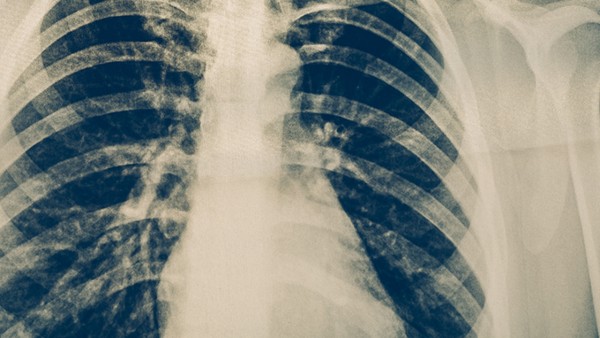

随着我国新冠肺炎病例的不断增加,相关诊疗指南也在不断更新。最新版本的诊断和治疗指南是国家卫生委员会2月8日发布的新型冠状病毒肺炎诊断和治疗计划(试行第五版) 与2月5日发布的第五版相比,修正版调整了利巴韦林的剂量,从原来的“成人第一剂4g,第二天每8小时一次,每次1.2g,或8mg/kgiv.每8小时一次”,调整为“500mg/次,静脉输入每天2-3次。

目前,利巴韦林是治疗新冠肺炎的经验药物。2003年非典期间,利巴韦林联合抗生素和糖皮质激素治疗非典型肺炎取得成功经验。具体方案是利巴韦林静脉给药400毫克,每天至少3次,直到病情稳定,然后改用1200毫克,每天口服2次,治疗7天。但目前还没有明确证据表明利巴韦林对新型冠状病毒有抑制作用,第五版修正版也在使用α-在干扰素、洛匹那韦/利托那韦的基础上,联合利巴韦林也参照2003年非典的经验性用药。